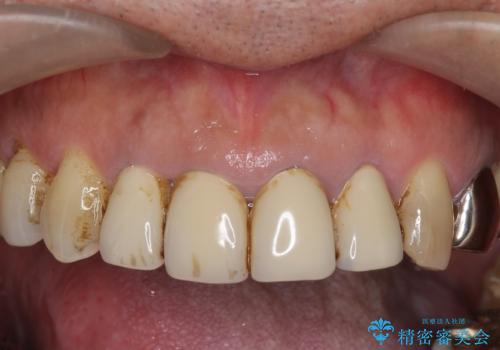

老朽化した前歯のクラウンやりかえ

- 10数年前に治療した上顎前歯のクラウンをやり替え、審美性を回復したいと希望され来院されました。

X線写真より問題のなかった根管治療は行わず、クラウンを除去し仮歯でを装着したのちジルコニアクラウンを製作していきます。

茶しぶの目立つ下顎前歯はPMTCを行うことで歯の自然な白さを回復しました。